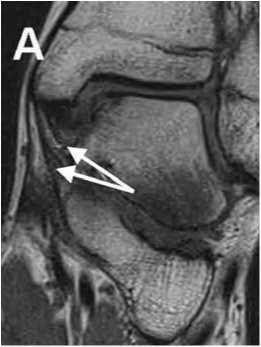

Контузия кости

В острую стадию контузия кости (костный ушиб) проявляется на МРТ в виде ретикулярных зон гипоинтенсивного сигнала в Т1 FSE и гиперинтенсивного сигнала в FS PD FSE, что связано с трабекулярными микропереломами, отеком и кровоизлияниями внутри костного мозга (рис. 6).

Костные контузии подвергаются обратному развитию в течение 8-12 недель. В большинстве случаев рентгенологические данные негативны.

Рис. 6. Контузия кости, 7-е сутки после Травмы.

A: FS PD FSE томограмма в коронарной проекции отображает зоны повышения сигнала костного мозга в области медиальной лодыжки и блока таранной кости (треугольные стрелки).

Б: на компьютерной томограмме в коронарной проекции нарушения целостности костной структуры не выявляется.

Выявление на МРТ костных контузий имеет большое клиническое значение, т.к. в случае продолжения стрессового воздействия на контуженную кость может произойти перелом [5].